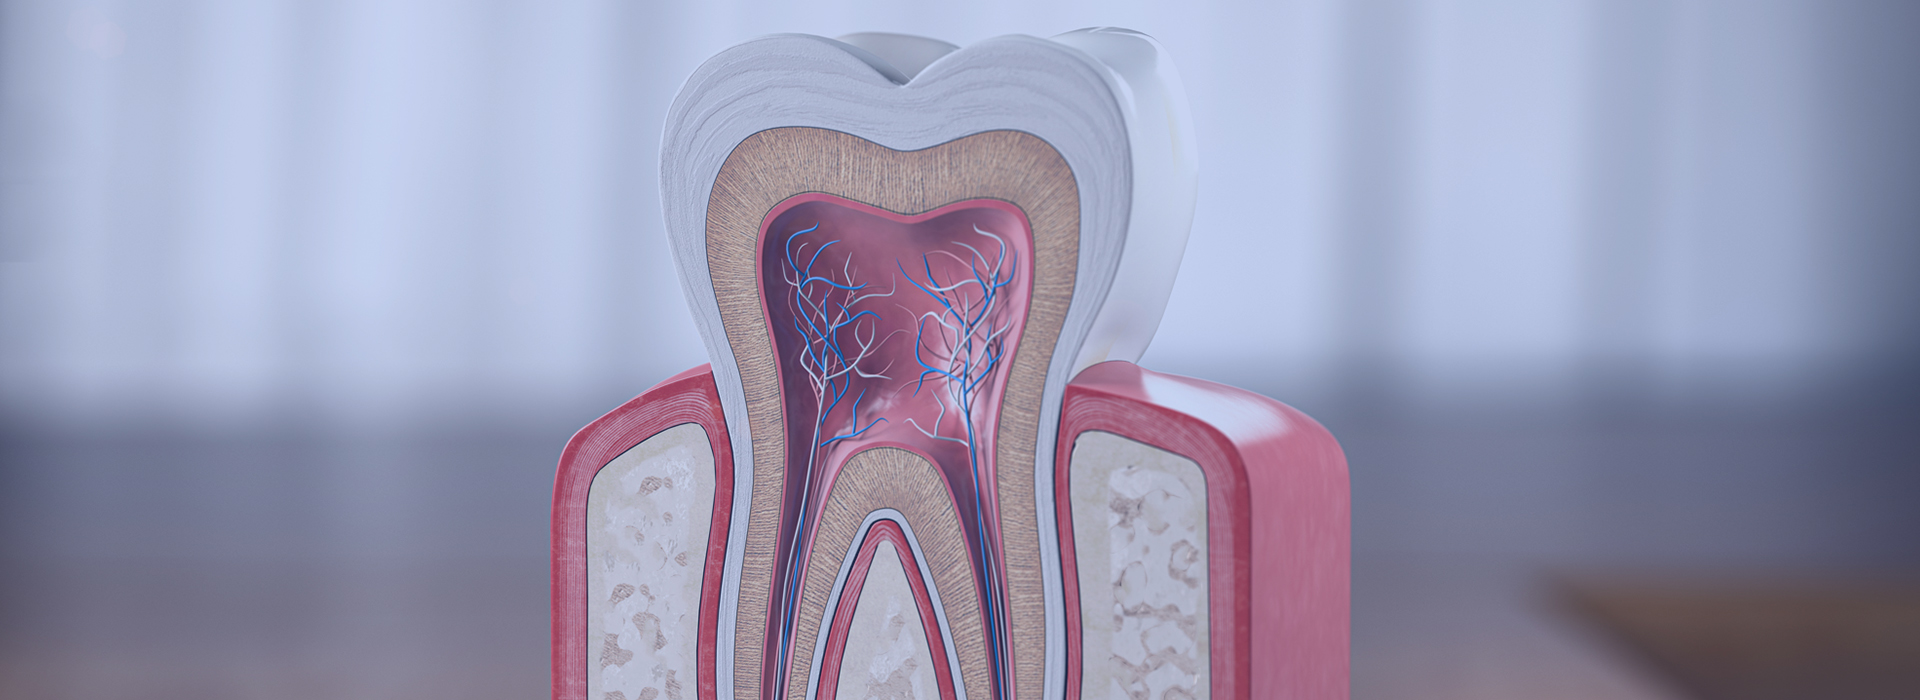

むし歯が進行して、むし歯菌による感染が神経にまで広がると、食べ物や飲み物がしみたり、ズキズキと痛んだりといった症状が現れます。そうなると、日常生活に支障が出るほど強い痛みが出たり、頬が赤く腫れることもあります。

以前は、歯を抜くしか治療法がありませんでしたが、現在は歯の神経を取り除き、歯の根を消毒して密閉する「根管治療」を選択できるようになり、歯を残せる可能性が広がりました。

むし歯は細菌による感染症です。放っておくと歯の表面から内部へと感染が進行します。ここでは5つの段階に分けてご説明します。